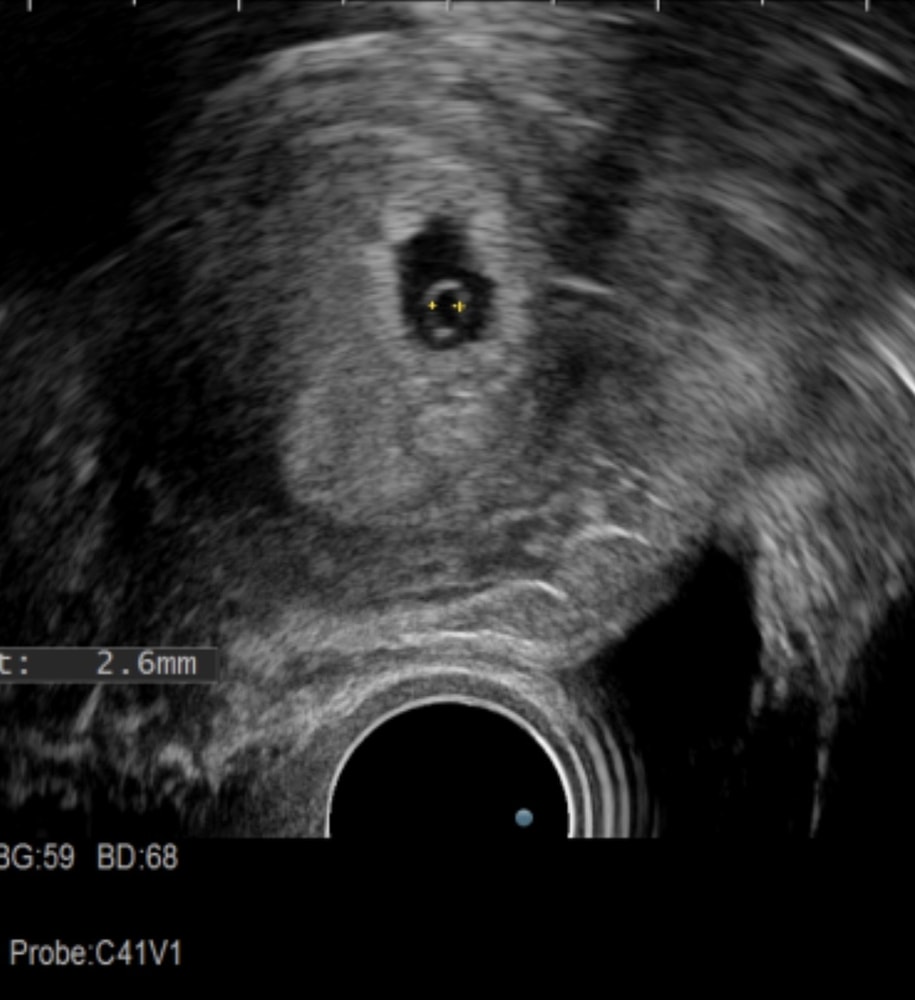

вот что написали : В полости матки визуализируется плодное яйцо 13,0 мм , желточный мешочек 2,6 мм и визуализируются два КТР 4,5 мм и 2,9 мм , в одном КТР размерами 2,9 мм визуализируется пульсация